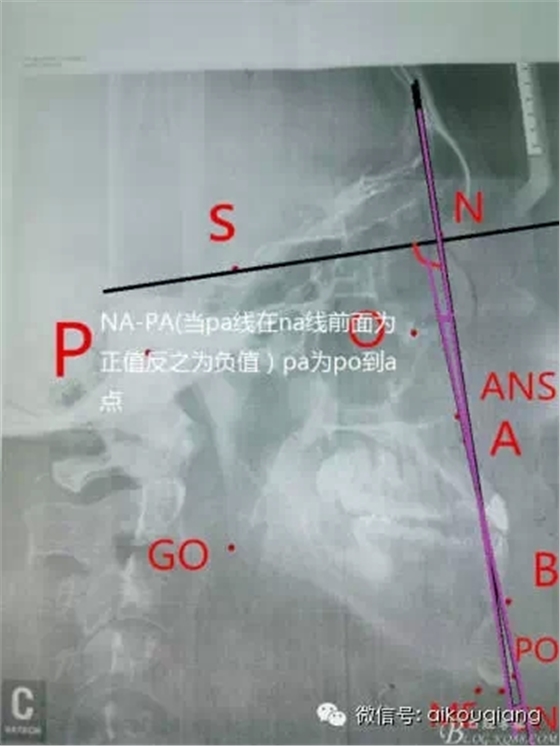

幾分鐘學(xué)會X線的測量分析圖